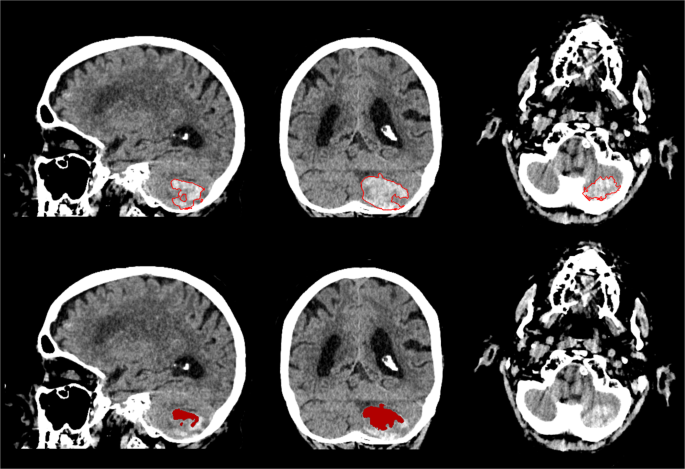

In general, the method was capable of segmentation of complex haemorrhages affected by image noise, heterogeneity due to varying stages of localised clotting and common imaging artefacts that may appear as haemorrhagic regions and cause false positive results, as shown in Figs. 1 and 4. However, two outliers that negatively affected the overall quantitative results could be identified. The first was a cerebellar haemorrhage located close to the occipital bone. This haemorrhage was affected by high intensity streaking artefacts causing heterogeneity with high intensity spots within the lower parts of the haemorrhage that resembled the surrounding skull. This artefact proved too severe for the method, resulting in a substantial undersegmentation in the final result. The second was a small intracerebral haemorrhage in the right precentral gyrus. A slight undersegmentation of the final result had a large impact on the quantitative measures because of the small volume of the haemorrhage. Both outlier results are depicted in Figs. 5 and 6.

Sagittal, coronal and axial view of outlier of the test dataset depicted in Fig. 3. Patient with cerebellar haemorrhage close to the skull with high density streaking artefacts and internal heterogeneity. Manual annotation of ICH boundary (top) and segmentation result of the proposed method (bottom).

Sagittal, coronal and axial view of outlier of the test dataset depicted in Fig. 3. Patient with small haemorrhage in the right precentral gyrus. Manual annotation of ICH boundary (top) and segmentation result of the proposed method (bottom).

We experienced difficulties with the method in two patients in the Radboudumc test dataset, as shown in Figs. 5 and 6. One of the patients had a total haemorrhage volume of less than 0.5 mL. In this case, a minor error in segmentation had a large impact on relative quantitative measures such as the DSC and AVD. Therefore, this negatively affected the overall quantitative results of the test dataset, as shown in Fig. 3. Another case was affected by image artefacts that largely impacted the appearance of the haemorrhage in terms of heterogeneity, leading to undersegmentation. However, the test dataset consisted of a variety of haemorrhages with differing shapes, internal heterogeneity and volumes, as shown in Table 5. Overall the method has proven to be robust to these varying factors.